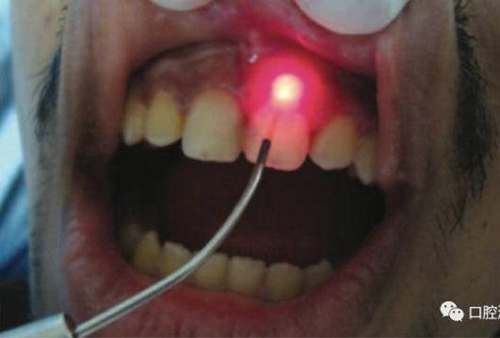

對瘺管位置進行激光氣化

激光治療后即刻